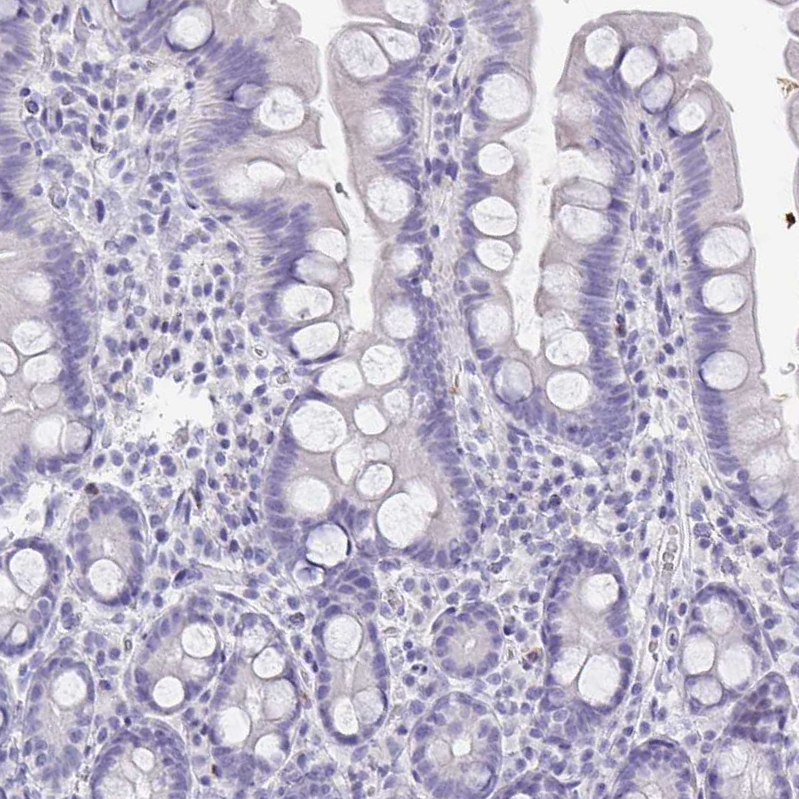

Immunohistochemistry analysis in human pancreas and skeletal muscle tissues using HPA060803 antibody. Corresponding PLA2G1B RNA-seq data are presented for the same tissues.